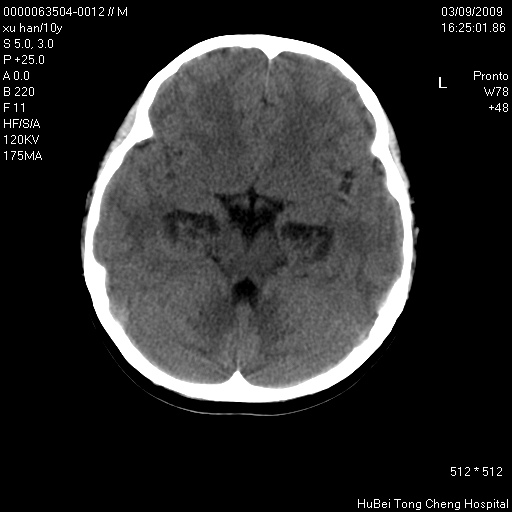

以下是引用道哥在2009-3-9 18:40:00的发言:[br]未见明显异常,必要时mr(dwi)成像。

以下是引用余辉在2009-3-10 11:01:00的发言:[br]考虑双侧海马急性缺氧性损伤